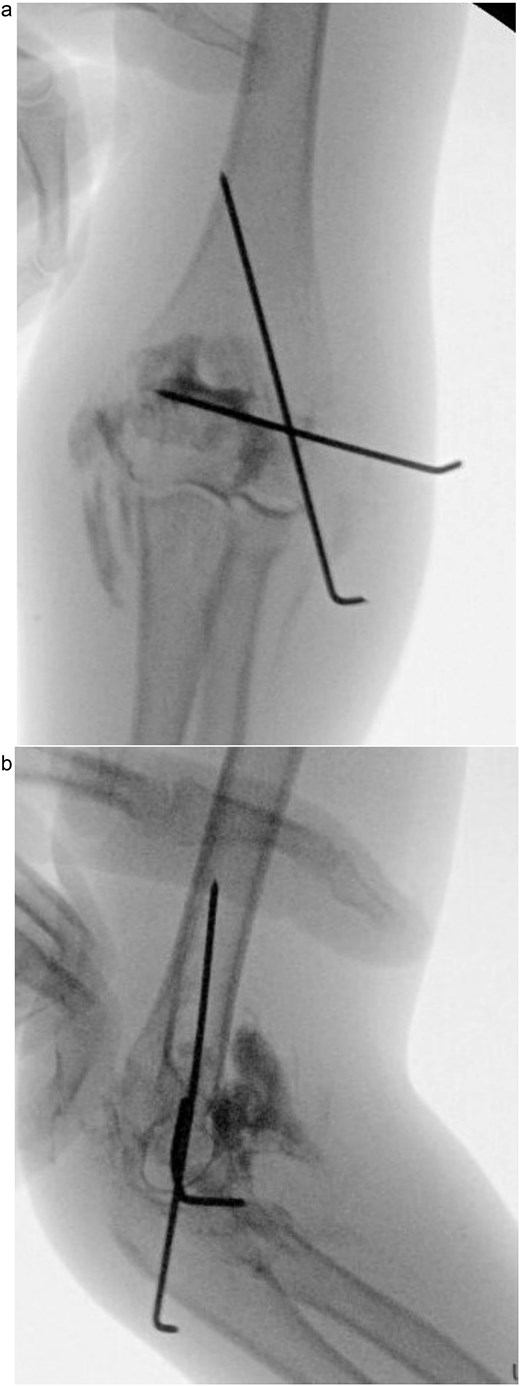

Under procedural sedation, closed reduction of the elbow dislocation was performed, restoring joint alignment and stability. However, post-reduction imaging showed persistent displacement of the lateral condyle fragment (Fig. 2a). The patient was subsequently taken to the operating room, where closed reduction of the condylar fracture was carried out under general anesthesia. As post-reduction displacement was less than 2–4 mm with intact articular cartilage, fixation was performed using two smooth Kirschner wires under fluoroscopic guidance. An arthrogram confirmed joint congruity and cartilage integrity (Fig. 3a). A long-arm posterior slab was applied with the elbow in <90° of flexion to minimize the risk of compartment syndrome (Fig. 4a).

(a) Immediate post-reduction anteroposterior radiograph showing restored joint alignment with persistent lateral condyle displacement. (b) Lateral view confirming maintained reduction of the ulnohumeral joint and residual separation of the lateral condyle fragment.